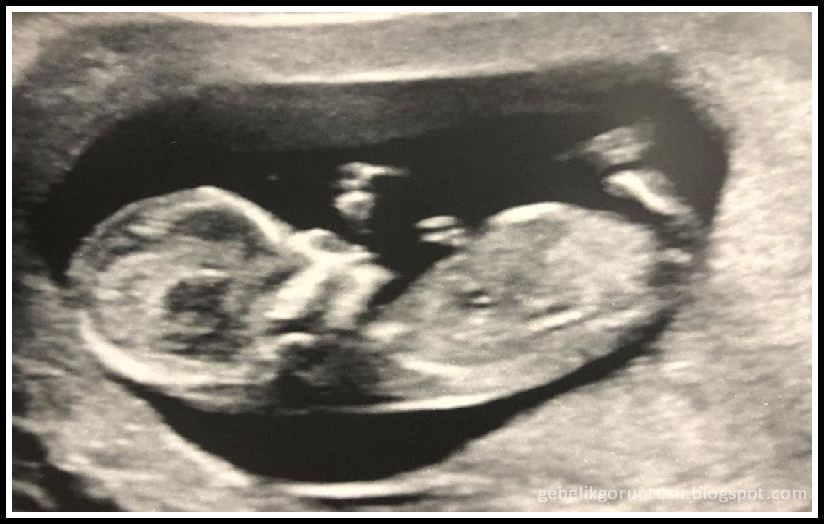

12 haftalık gebelik ultrason görüntüsü

| 12 haftalık gebelik görüntüsü |